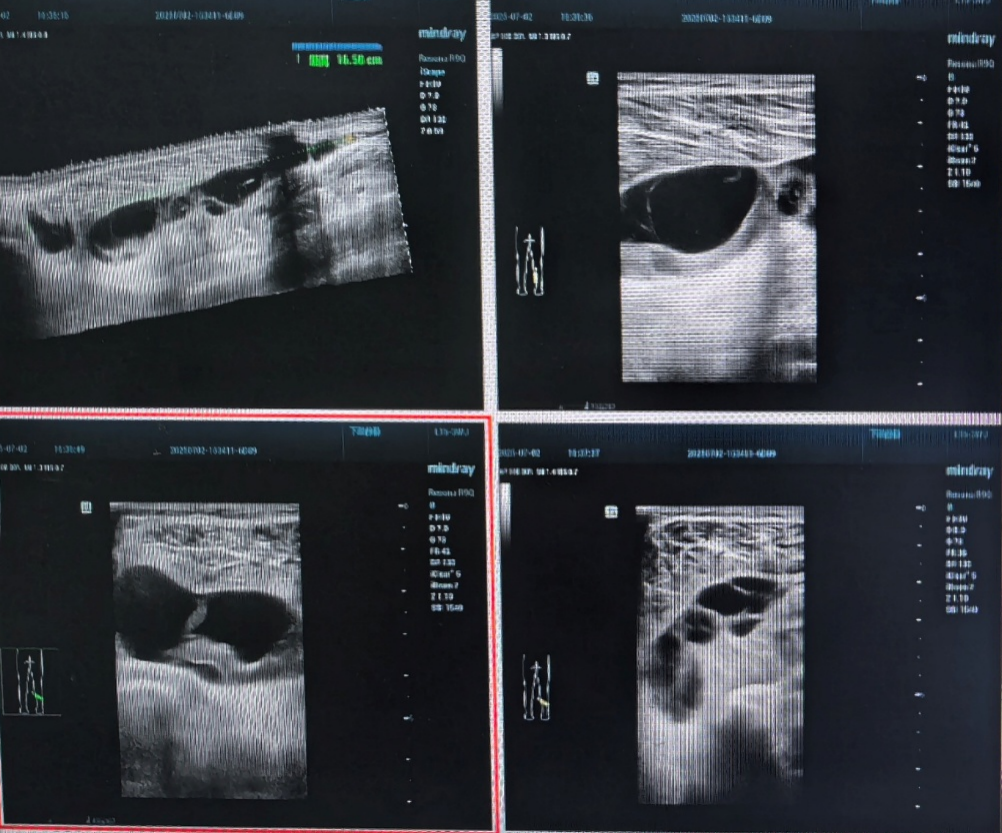

患者,男性,因左小腿持续疼痛入院。初步超声检查显示,其小腿肌间隙内存在一个长达16厘米的异常肿块(图1,图3),疑似血肿,穿刺后显示暗红色血性液体(图3)。为了明确诊断并制定最佳治疗方案,在骨科侯俊主任医师领导下,杨元勋副主任医师团队迅速行动,组织多学科会诊,邀请骨科、超声科及齐鲁医院骨科专家共同研讨。

图1:超声显示:小腿肌间隙血肿

在齐鲁医院骨科郭永园教授的悉心指导下,手术团队精心准备,确保每一个细节都达到最佳状态。手术过程中,利用先进的超声设备,为关节镜手术提供了精准的导航。通过关节镜在微小的切口下成功找到了囊肿(图4),并进行了精准切除(图5)。整个手术过程出血少、创伤小,患者术后恢复迅速。

图4:超声引导关节镜准确进入囊腔内部